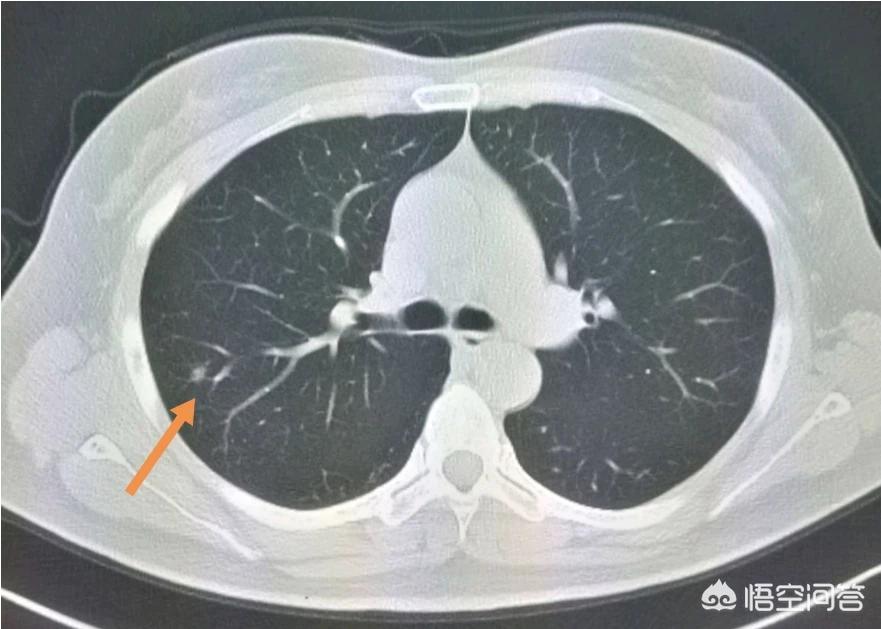

这是一位老烟民,咳嗽,痰里带血丝,CT发现右肺下叶后基底段支气管壁局部增厚,呈指套征,支气管镜证实为早期肺鳞癌。